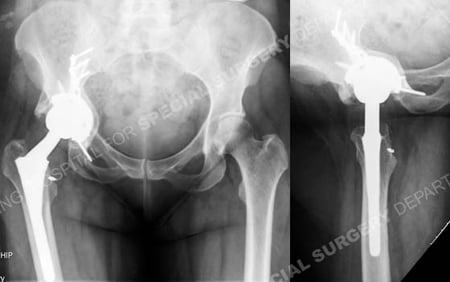

A 46-year-old female sustained a periprosthetic acetabular fracture 1 month following a revision Total Hip Arthroplasty (THA) procedure. She was referred to David L. Helfet, MD at the Orthopedic Trauma Service of Hospital for Special Surgery for definitive management of her periprosthetic acetabular fracture. Open Reduction and Internal Fixation (ORIF) was performed with placement of 2 pelvic reconstruction plates and screws and bone graft. She returned for regular follow-up and healed uneventfully and at 6 months following surgery she presented with excellent radiographic and clinical results including a healed periprosthetic acetabular fracture, resolution of hip pain, and return to her activities of daily living.

Anteroposterior and lateral radiographs at 6 months illustrating a healed periprosthetic acetabular fracture.